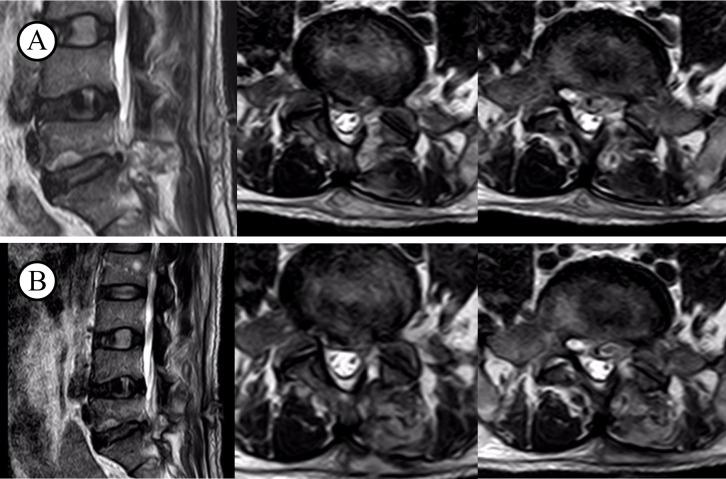

The most common clinical symptoms included localized back pain, neurological deficits, and fever, though these lacked specificity. MRI proved valuable in diagnosing early infections. The majority of cases exhibited elevated levels of inflammatory markers, such as CRP and ESR. The treatment plan included early surgical intervention with debridement and internal fixation, along with extended antibiotic therapy.

最常见的临床症状包括局部背痛、神经功能缺损和发热,不过这些症状缺乏特异性。MRI被证明在早期感染诊断中具有重要价值。大多数病例炎症标志物水平升高,如CRP和ESR。治疗方案包括早期手术清创及内固定干预,以及延长抗生素治疗。